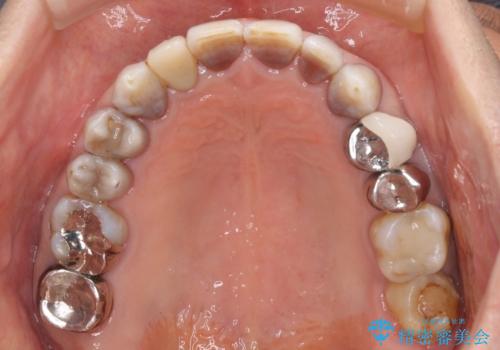

インビザラインは四六時中上下のマウスピースを介した咬合状態となるため、治療過程にて奥歯が接触しないという状態が続くことがあります。

奥歯の非接触は機能面において大きな障害であるため、この問題を解決しない限り矯正治療を終えることはできません。

インビザラインでの矯正治療が長期化してしまう要因の1つです。